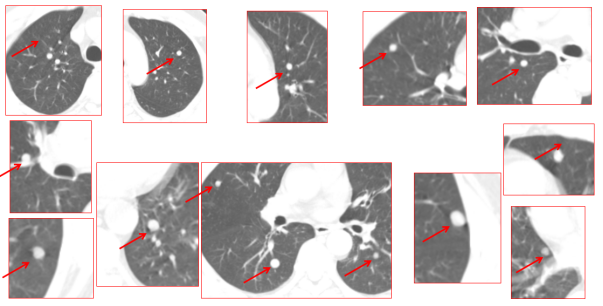

治疗前(2023年2月24日)4D-CT显示,正常呼吸状态下双肺16个转移灶随呼吸运动明显移位。在HFOV呼吸管控下,膈肌运动控制在1mm以内,靶区位置极其稳定。2023年2月,患者在全身麻醉联合高频振荡呼吸机辅助呼吸管控下,针对左肺8个、右肺8个共16个转移灶一次性行重(碳)离子精确放疗,费用算两个部位共25万。

上图为治疗前左右肺共16个转移病灶,红箭头指示肺转移结节

疗效评估:治疗前(2023年2月27日)双肺16个转移灶清晰可见;治疗后16个月(2024年6月14日),所有肿瘤完全消失,放射性反应进入纤维化期,患者一般情况良好。这一结果令人振奋—16个转移灶一次性全部灭活,效果显著,耐受良好。

结论:对于肝癌术后双肺多发转移(16个病灶)这类常规治疗手段难以奏效的病例,重(碳)离子放疗联合全麻下高频振荡呼吸管控提供了一种全新的、有效的治疗方法。本病案证明,即使是多达16个的肺转移灶,在精准的呼吸管控下,重(碳)离子放疗仍可实现一次性全部灭活,为晚期肿瘤患者创造了新的生机。